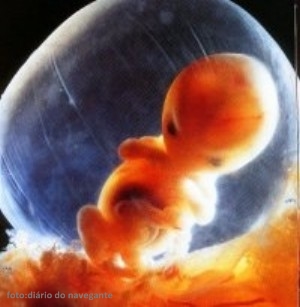

8 Semanas de Gestação

Sua 8a semana começa

- Nessa fase de desenvolvimento fetal as pálpebras e o lábio superior começam a aparecer, já as orelhas tomam uma forma mais familiar.

Sim, seu bebê cresce e se desenvolve a cada dia! E de acordo com o desenvolvimento fetal padrão, na 8a semana de gestação as pálpebras e o lábio superior começam a surgir e as orelhas tomam uma forma mais familiar1. Os botões dentários já dão as caras também e os vasos sanguíneos podem ser vistos com facilidade através da pele que é bem fininha.

Com 8 semanas de gravidez, o seu pescoço já está mais ereto, seus dedinhos individualizados e a cauda não existe mais! Agora ele mede cerca de 1,6 cm e é do tamanho de um grão de feijão. O bebê cresce rapidamente e é muito importante que a mamãe esteja tomando ácido fólico para auxiliar no desenvolvimento saudável2.

Com 8 semanas de gestação, o bebê se movimenta bastante dentro do útero da mamãe, porém não é possível senti-lo ainda. Há um grande espaço entre a parede uterina e o feto. Vai ser possível sentir somente quando o bebê começar a encostar nesta parede e seus movimentos serão percebidos através de terminações nervosas. Ainda assim, a mamãe jura sentir alguma coisa, mas normalmente é algo relacionado aos movimentos do próprio útero ou até mesmo dos gases!